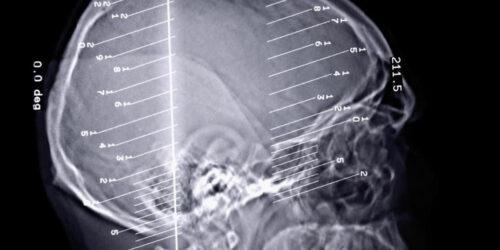

The human body can perform all its functions seamlessly when every organ of the body works in unison to perform the task. A slight change in the functions of the organ can disrupt the entire functioning of the body. Epilepsy seizures are a kind of disorder that occurs when we there is a problem in our brain’s electrical system.